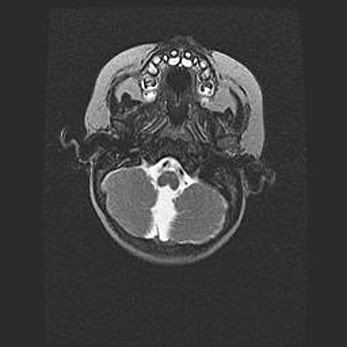

Аномалия Денди-Уокера. Признаки гипоплазии мозолистого тела.

Возраст: 5 месяцев 3 дня

Вес: 5550 г

Пол: мужской

Окружность головы: 39 см

Срок гестации: 40 недель

Аномалия Денди-Уокера – это порок развития головного мозга, для которого характерна триада симптомов: гипотрофия или аплазия червя мозжечка и/или полушарий мозжечка, расширение четвёртого желудочка с формированием ликворной кисты задней черепной ямки, гипертензионная гидроцефалия различной степени.

Гипоплазия мозолистого тела относится к дефектам внутриутробного этапа развития мозговой ткани, возникающим в процессе закладки структур головного мозга, что происходит на начальных этапах развития эмбриона.